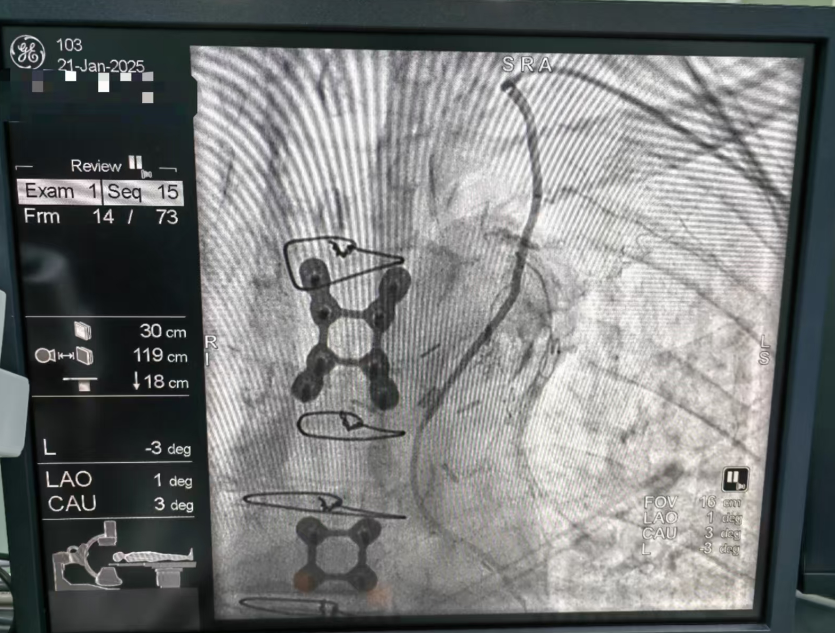

华润武钢总医院心血管内科与瑞州医院达成学科共建协议。2025 年 1 月 21 日,心血管内科副主任医师蔡绍乾成功与瑞州医院心血管内科团队完成该院首例冠状动脉桥血管造影术。

在完善相关术前检查排除相关手术禁忌症后,刚刚到达瑞州医院的蔡绍乾医生与瑞州医院心血管内科团队一起为患者行局麻下冠状动脉桥血管造影术。凭借着丰富的临床经验,蔡医生和心血管内科团队术中一路探寻,最终发现内乳动脉为桥血管,完美造影,手术顺利结束。